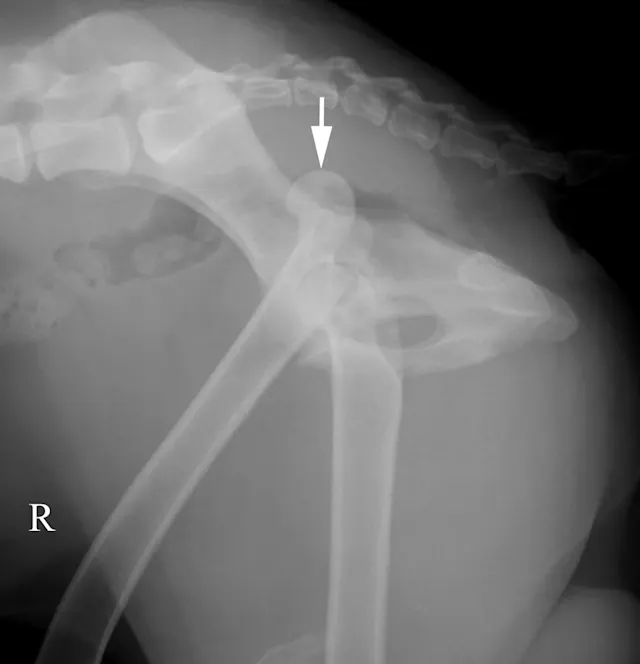

The lateral radiograph is obtained with the patient in lateral recumbency and the hindlimbs separated (Figure 3A). A foam positioning device is placed between the limbs or under the "up" leg to keep the femur parallel to the table. The forward limb (typically the limb closest to the imaging plate) is labeled. The corresponding normal lateral radiograph is shown in Figure 3B. In Figure 3C, the femoral head (arrow) of the cranially positioned right limb is luxated craniodorsally.